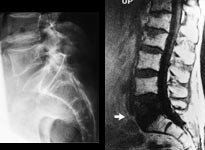

Symptomgivende metastaser til columna opptrer imidlertid i ca. 5 % hos pasienter med maligne svulster. MR er svært følsom for metastaser (20) og det er viktig å huske at normalt utseende konvensjonelle røntgenbilder ikke kan utelukke selv uttalte destruktive skjelettforandringer (fig 7).